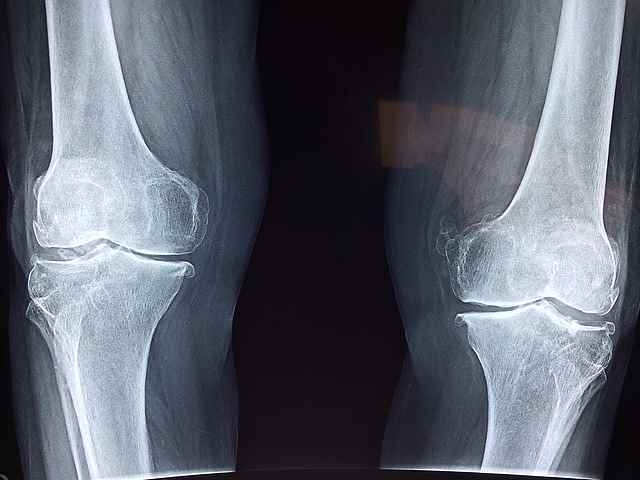

관절염은 주로 관절에 영향을 미치는 만성 염증성 질환으로, 통증, 부종, 경직 및 이동성 저하를 초래합니다. 이는 골관절염과 류마티스 관절염이 가장 일반적인 유형이며 광범위한 장애를 포함합니다. 관절염은 모든 연령, 성별 구분 없이 사람들에게 영향을 미칠 수 있지만 노인들에게 더 널리 퍼져 있습니다. 관절염의 정확한 원인은 유형에 따라 다르지만 유전자, 면역계 기능 장애, 부상 및 생활 습관 요인과 같은 요인이 관절염이 생길 수 있습니다. 관절염의 효과적인 관리에는 종종 약물, 물리 치료, 생활 습관 수정 및 경우에 따라 외과적 개입이 포함됩니다. 조기 진단 및 치료는 관절염을 앓고 있는 개인의 관절 손상을 최소화하고 삶의 질을 향상시키는 데 중요합니다.

관절염으로 인한 관절통은 둔한 통증부터 날카롭고 찌르는 듯한 느낌까지 지속적인 불편함으로 나타납니다. 통증은 움직임이나 활동 기간이 길어지면 악화되는 경향이 있으며, 특히 휴식 이후에 두드러집니다. 무릎, 엉덩이, 척추와 같은 체중을 많이 받는 관절뿐만 아니라 손과 발의 관절과 같은 작은 관절에도 흔히 영향을 미칩니다.

8. 관절 기형

관절염의 진행 단계에서, 장기간의 염증과 관절 구조의 손상은 돌이킬 수 없는 관절 기형으로 이어질 수 있습니다. 이러한 기형은 관절 정렬 불량, 뼈 스퍼스, 그리고 관절 모양의 변화를 포함할 수 있고, 그로 인해 심각한 기능 장애와 장애가 발생할 수 있습니다.